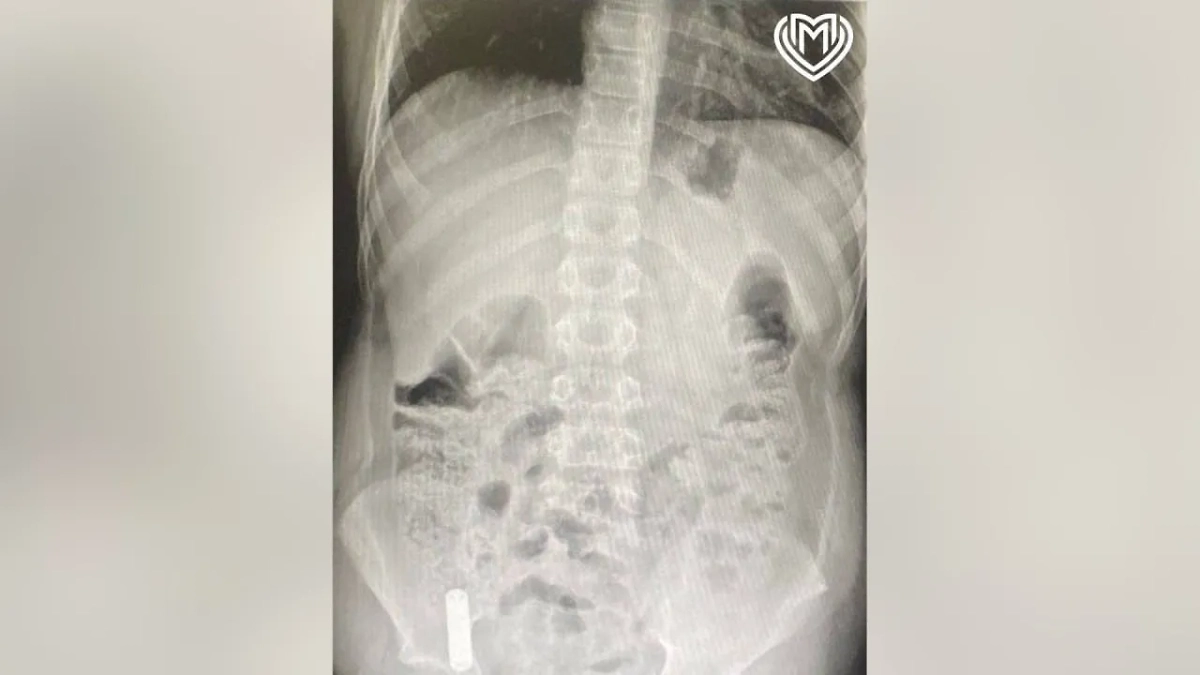

Рентген показал, что батарейка застряла в илеоцекальном углу слепой кишки. Фото © Предоставлено Life.ru

По словам заведующего хирургическим отделением Игоря Хворостова, рентген показал, что батарейка застряла в илеоцекальном углу слепой кишки. Для её извлечения хирурги применили инновационный подход: сначала провели лапароскопию, чтобы оценить состояние и расположение инородного тела, а затем с помощью эндоскопии и специальной петли аккуратно удалили литиевую батарейку. К счастью, она осталась целой, что позволило избежать химического ожога.